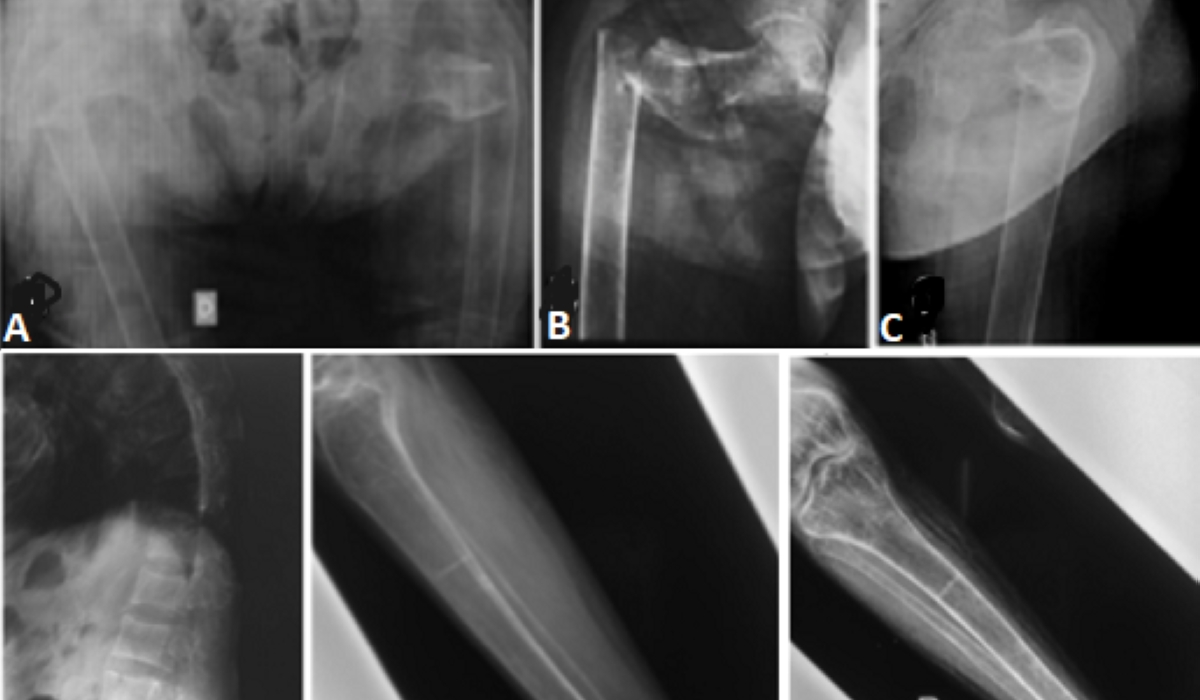

Osteomalacia is a disease characterized by softening of bones due to deficiencies in phosphate, calcium, and vitamin D, or from calcium resorption, affecting bone mineralisation. The most common cause of osteomalacia is a deficiency of vitamin D, which is normally mostly derived from exposure to sunlight, and to a lesser extent, from diet. Dietary sources of vitamin D include oily fish, like salmon and sardines, red meat, egg yolk, curd, cheese, and soya beans. Other than fish, meat products pose various health risks and should be consumed in limited quantities. Poor absorption of vitamin D is yet another cause of deficiency. It can occur due to diseases like malabsorption syndrome, Crohn’s disease, TB, chronic kidney diseases, etc. Some drugs like laxatives, steroids, and cholesterol-lowering drugs, also cause a deficiency of vitamin D. Obesity is also a risk factor for vitamin D deficiency and osteomalacia. Some individuals may have osteomalacia due to a hereditary deficiency of vitamin D3. Symptoms include diffuse body pains, muscle weakness, and increased fragility of bones. The spine, pelvis, and legs are particularly affected. Initially, pain occurs during some strenuous activity like climbing stairs or walking long distances. But with the progress of the disease, pain may occur when even walking a small distance or after some minor work. The small bony joints of the backbone can collapse, thus diminishing the stature. The gait of an individual may become waddling. Not only the bones of the body, but even the teeth become brittle. The affected bone can become deformed or break spontaneously, without any trauma (pathologic fracture). Elderly persons, particularly those who are house bound, are more vulnerable to vitamin D deficiency and resultant osteomalacia, as this population has little exposure to sunlight. Besides, the ability to synthesise vitamin D from sunlight and its absorption from the intestine declines with age, thus further aggravating the risk of deficiency in these persons. Other high-risk groups are people who work night shifts and rest during the day, those with surgery involving intestines, people who migrate from warm to cold climates, and women who keep the entire body and face covered with a veil. During pregnancy, the requirement of calcium is increased, if not fulfilled, it makes the bones soft and the newborn prone to rickets. Regular use of alcohol interferes with the metabolism of vitamin D and can result in its deficiency. Osteomalacia is different from osteoporosis, though both cause weakening of the bones. In osteoporosis, the bone mineral density and bone mass reduce, which reduces the strength of the bones. It is a degenerative bone disease, mostly occurring with advancing age, and remains asymptomatic in its early stages. Whereas osteomalacia occurs due to a deficiency of vitamin D, it causes problems with bone formation and softening of the bones. It can occur in children as well when it is called rickets. Diagnosis is made based on clinical features, low blood calcium, vitamin D3, and phosphate levels. X-rays and or scans will show softening of the bones. Nutritional osteomalacia can be treated very well by oral or injectable vitamin D3 supplements. If it is secondary to some disease, treatment of the disease process helps cure osteomalacia as well. Osteomalacia that occurs because of adverse effects of some drugs can be stopped or reversed if the offending drug is stopped in the early stages. Prevention lies in a diet rich in vitamin D and adequate exposure to sunlight. Dietary substances containing vitamin D like fish, egg yolk, cheese, curd, red meat, etc., should be part of daily meals. During pregnancy and the first few months of breastfeeding, it is recommended to take supplements of calcium and vitamin D. This prevents the softening of bones during or after pregnancy and even in the newborn. Alcohol and tobacco are best avoided. Regular physical exercise like walking, running or lifting weights, helps to strengthen muscles and improve strength of limbs. However, strenuous exercise should be avoided. Dr Rachna Pande is a specialist in internal medicine. rachna212002@yahoo.co.uk